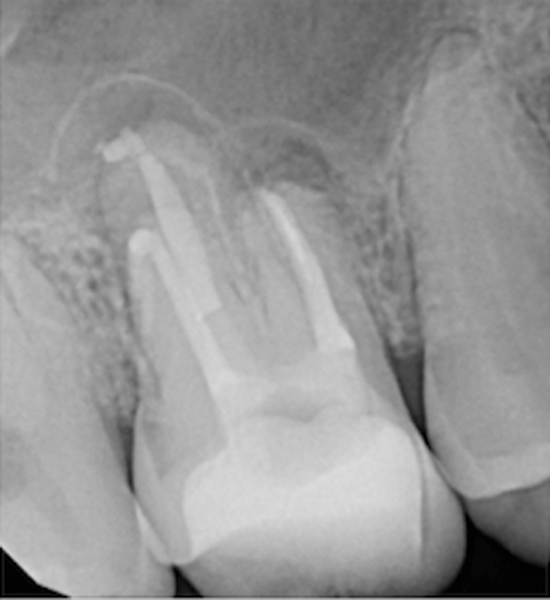

Figure 12. Postoperative radiography after full pulpotomy was performed. Courtesy of Dr. Guillaume Jouanny.

Figure 12

Figure 13. Tooth was asymptomatic at 1-year follow-up. Courtesy of Dr. Guillaume Jouanny.

Figure 13

In this case, the tooth tested vital but showed clinical signs of irreversible pulpitis. Treatment with a full pulpotomy was chosen to improve the chances the remaining pulp would survive and remain healthy. The preoperative radiograph in Figure 11 shows extensive caries in the tooth and a slightly widened apical periodontal ligament. A full pulpotomy was performed using the BC putty (Figure 12). After the putty set, a coronal restoration was placed, and an immediate postoperative radiograph was taken and viewed. At the 1-year follow-up, the tooth was asymptomatic, and the radiograph showed continued root development (Figure 13), a healthy apical periodontium, and, importantly, no calcifications in the remaining pulp (as is often seen with a calcium hydroxide therapy). A radiograph taken of the contra-lateral tooth showed similar root development (Figure 14).